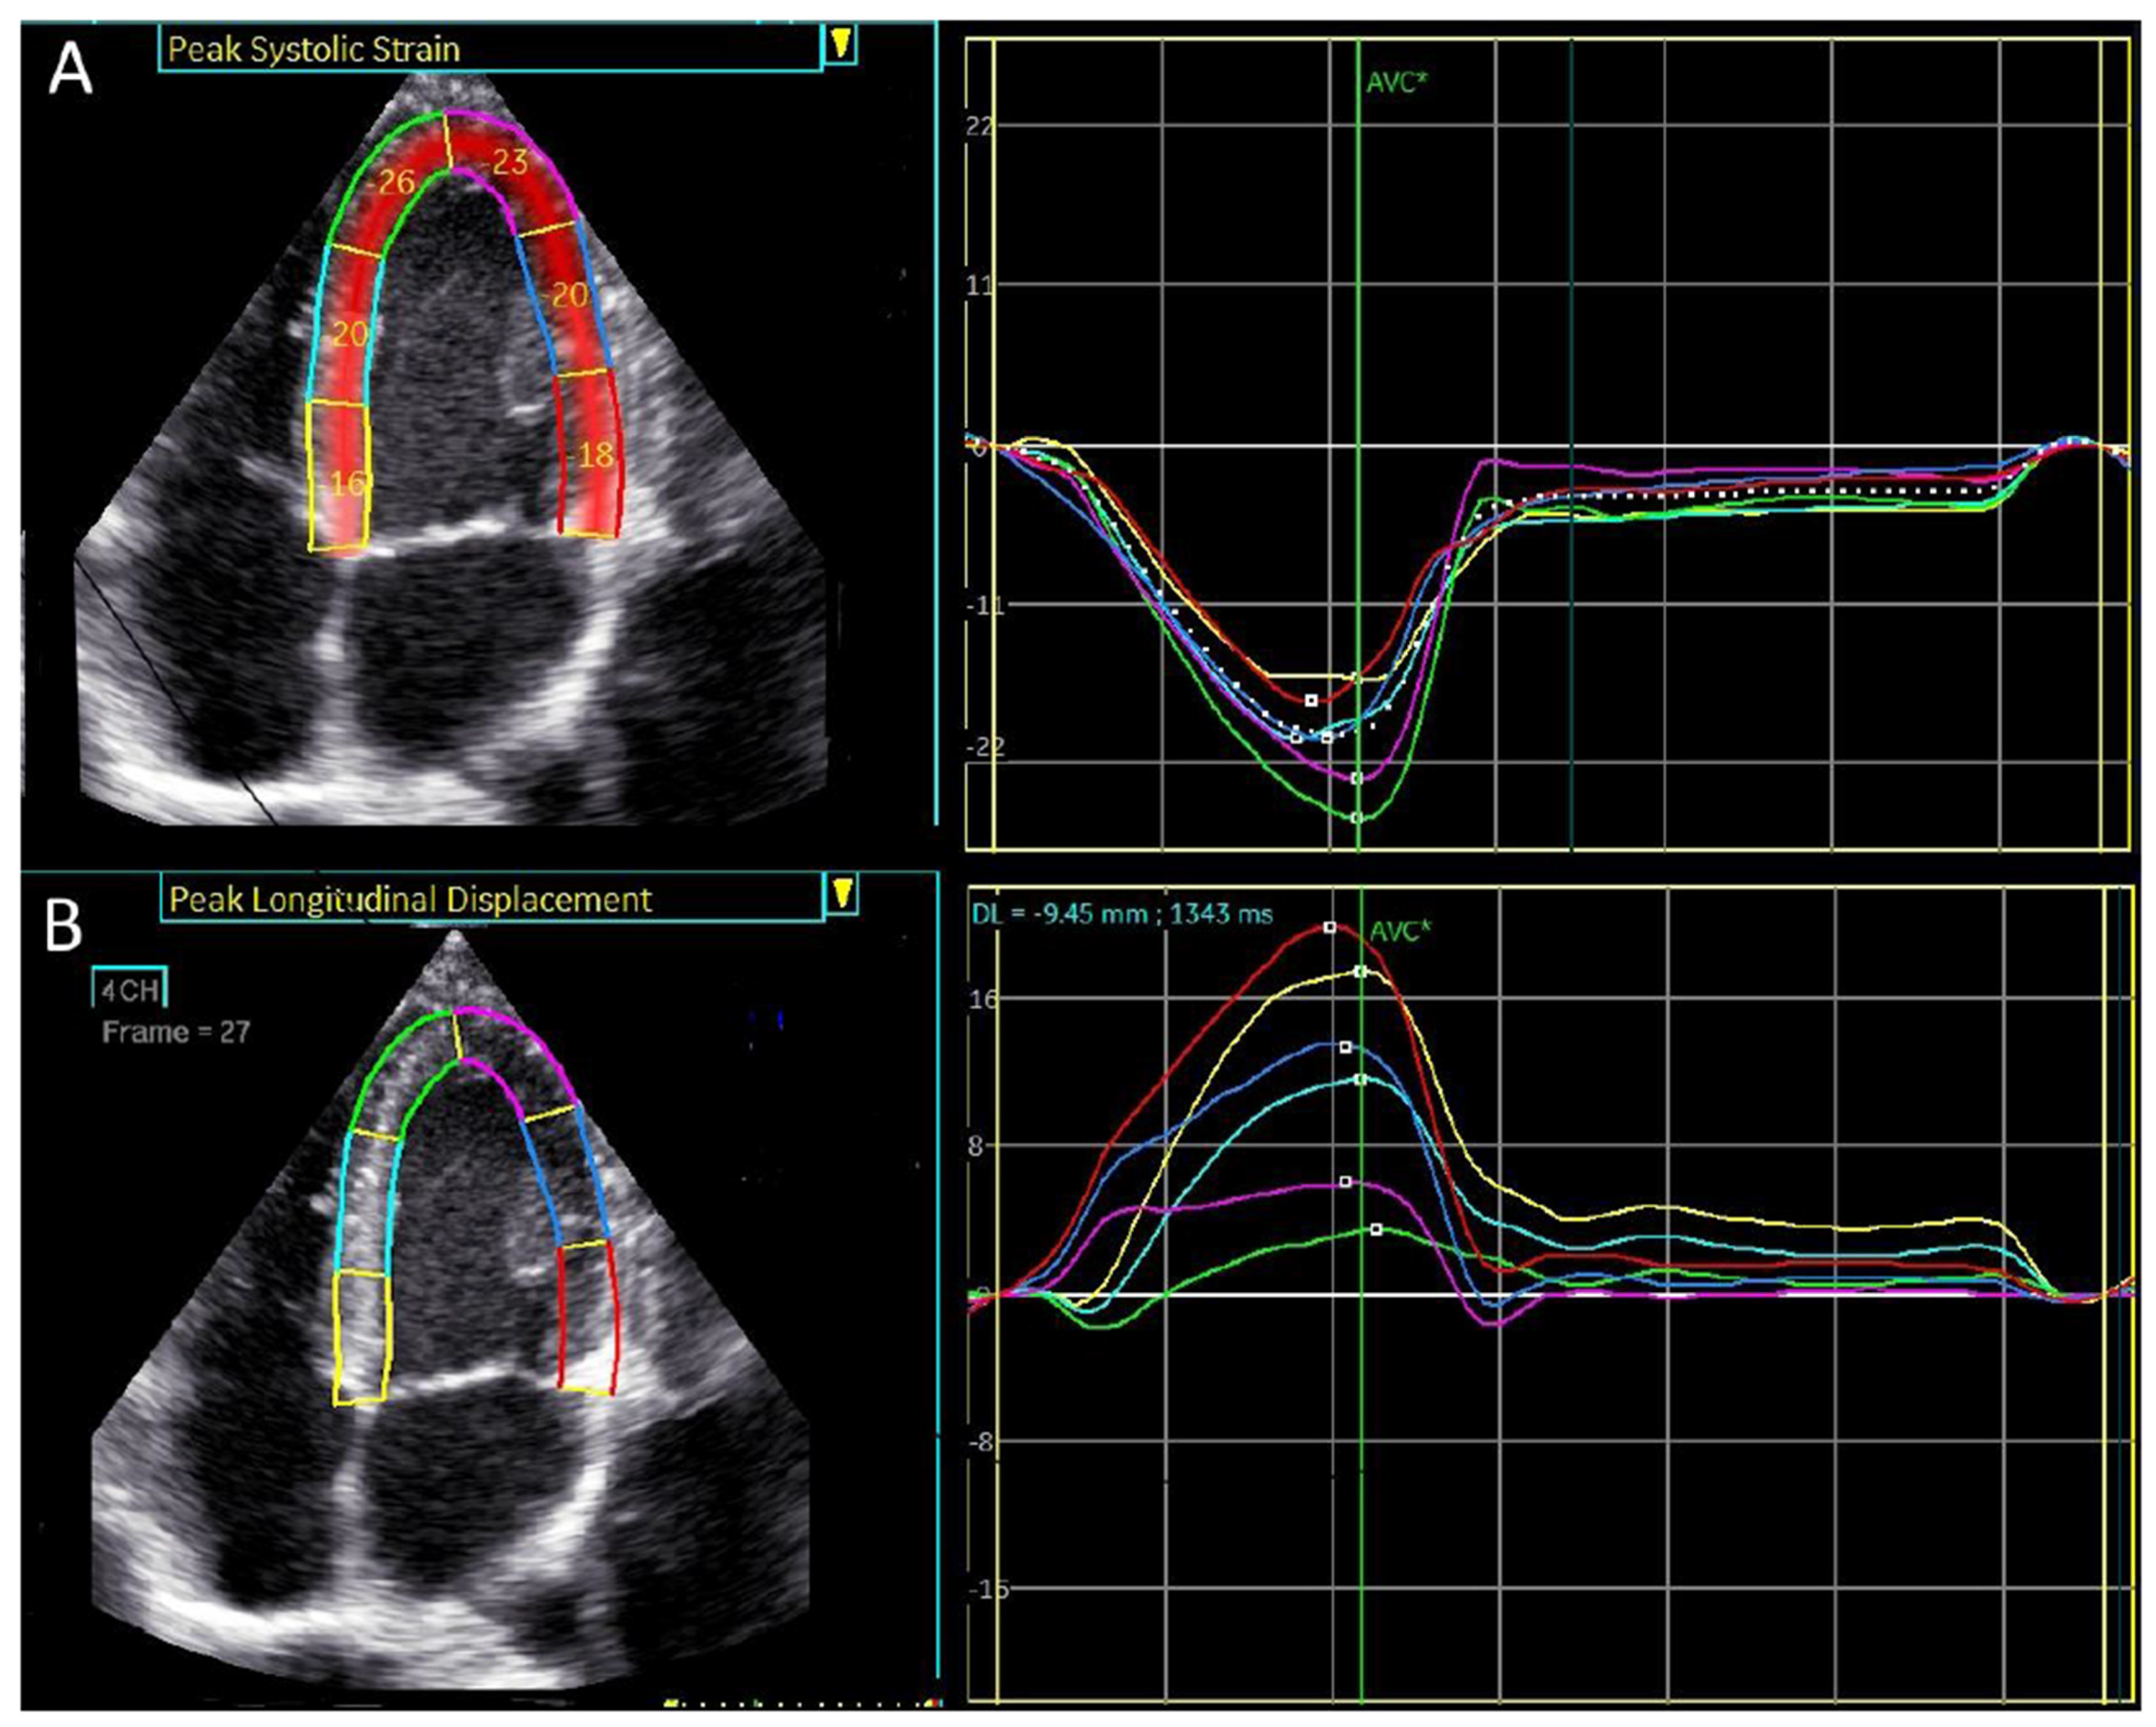

An example of peak systolic regional longitudinal displacement and strain for a 27-year-old football player is shown in Figure 5A,B. In contrast to the peak systolic strain, which exhibits a basal-to-apical gradient, peak longitudinal displacement is highest in the basal segments and lowest in the apical segments, demonstrating a reversed basal-to-apical gradient.

Figure 1. 4-chamber apical view. Regional longitudinal strain and displacement of a normal subject. (A) Regional peak systolic longitudinal strain has a negative direction. (B) Regional peak systolic longitudinal displacement has a positive direction.

Figure 5. A visual plot of the normal peak longitudinal displacement and strain of 27-year-old football player. (A) Peak longitudinal displacement is highest in the basal segments and lowest in the apex. (B) Peak longitudinal strain is lowest in the basal segment and highest in the apex.